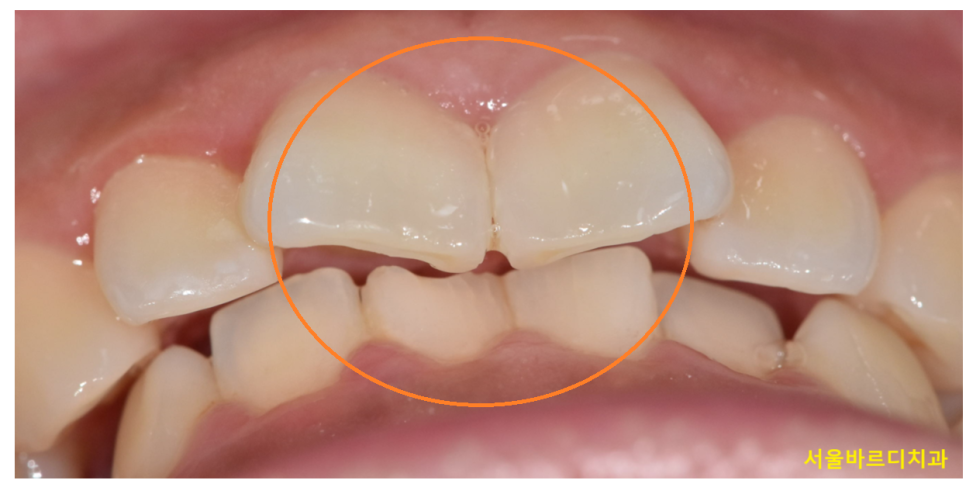

이를 앙 물었을 때 아래 치아가 거의 보이지 않거나

윗니가 아랫니를 과도하게 덮는 모습이죠.

어떤 경우에는 아랫니가 윗 치아와 닿아

갈려 나가는 마모된 모습을 관찰할 수 있습니다.